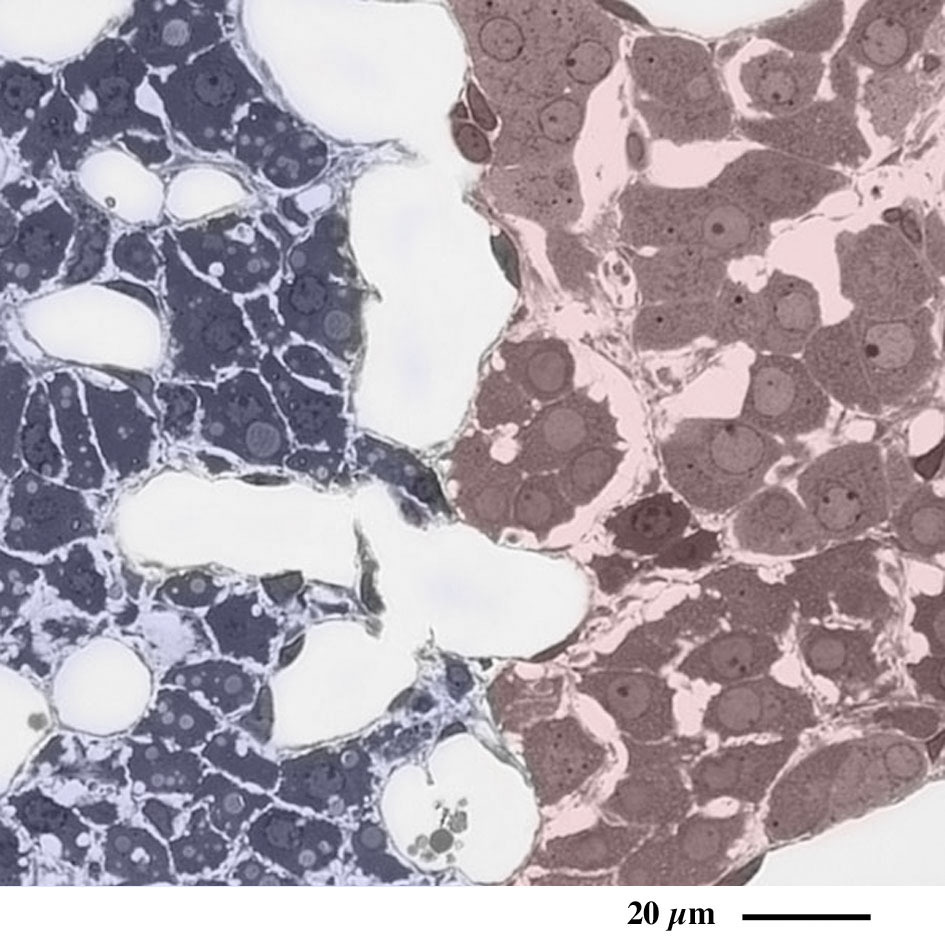

エポン樹脂準超薄切片のトルイジンブルー染色光学顕微鏡画像

Light microscopic image of semithin epoxy resin section with toluidin-blue staining

副腎皮質網状帯(左:青)/副腎髄質(右:赤)